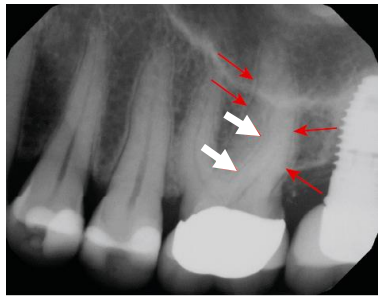

Com relação ao exame radiológico em

endodontia, a imagem abaixo, de uma projeção

periapical padrão, mostra os contornos da

superfície radicular com o espaço do ligamento

periodontal e a lâmina dura adjacente ao redor

das raízes dos pré-molares e do primeiro molar,

estruturas que o dentista deve visualizar para

avaliar a saúde periapical. O que as setas brancas

estão indicando?

(TORABINEJAD, Mahmoud; FOUAD, Ashraf F.; SHABAHANG, Shahrokh. Endodontia: princípios e práticas. 6. ed. Rio de Janeiro: GEN/ Guanabara Koogan, 2022. p. 45.)